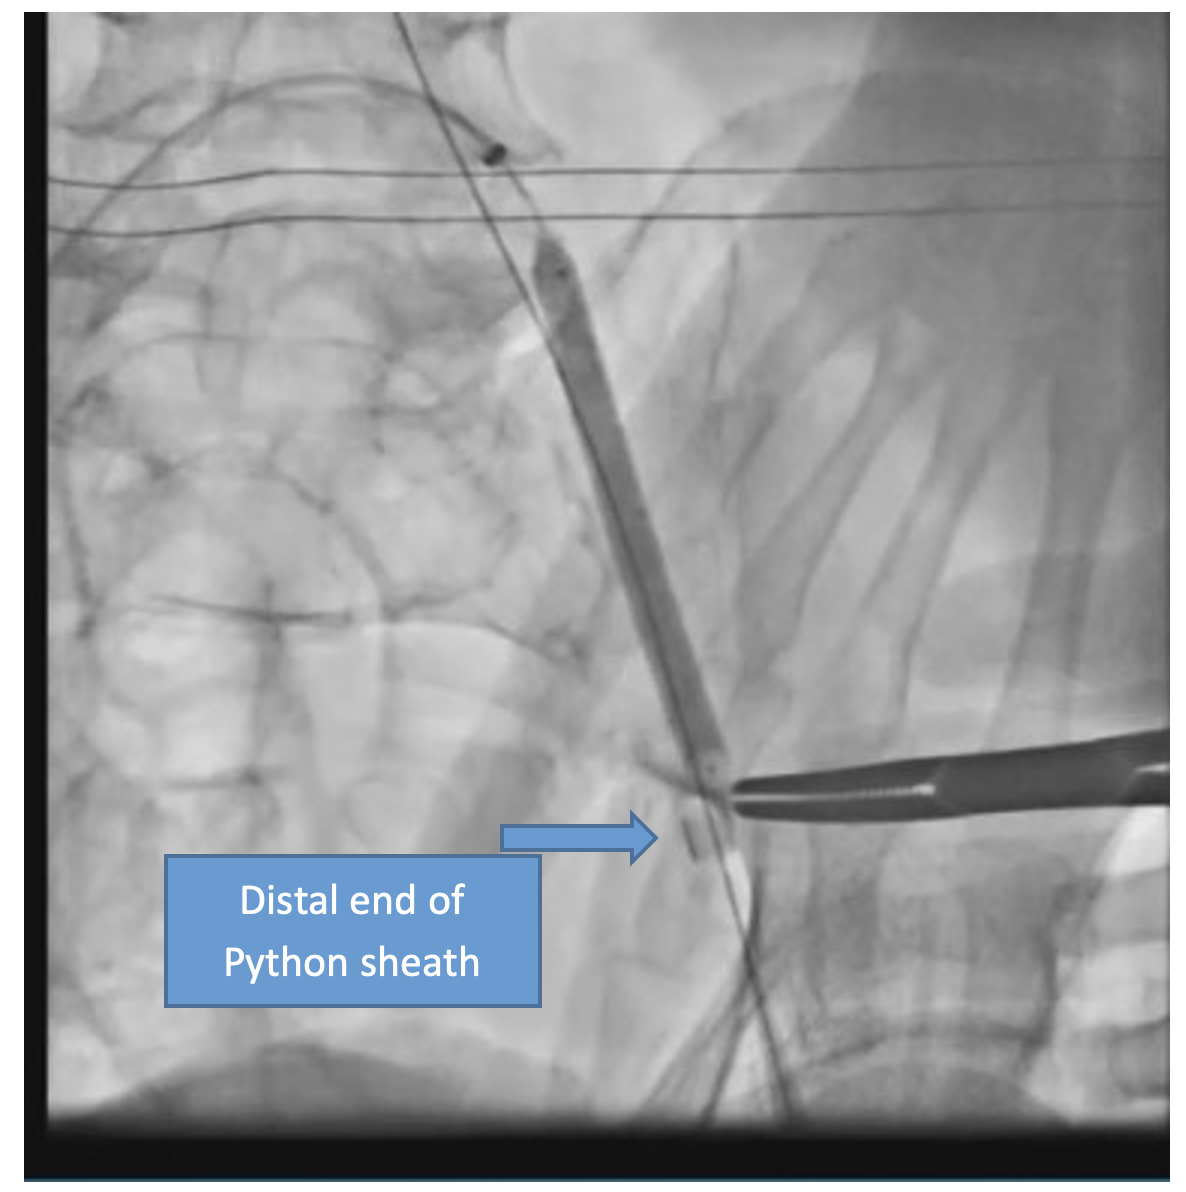

The patient was taken up for TAVR via a left common femoral artery (CFA) approach. The aortic valve was crossed (Figure 1A), and pre-dilatation was done using an 18-mm x 40-mm Mammoth balloon catheter (Meril Life Sciences) (Figure 1B). A 24.5-mm Myval transaortic valve (Meril Life Sciences) was introduced inside a Python expandable introducer sheath (Meril Life Sciences). However, the device could not be negotiated in the distal external iliac artery (EIA) due to calcium. The arrow in Figure 2A shows calcium in the distal EIA. The artery forceps depicts a marker for the distal end of the Python sheath. The sheath was withdrawn in the distal EIA; right CFA puncture was done and a 7F crossover sheath was placed. Intravascular lithotripsy (IVL) was done using a 7-mm x 60-mm IVL balloon; 30 pulses at 4 atm followed by 30 pulses at 6 atm were given (Figure 2B).